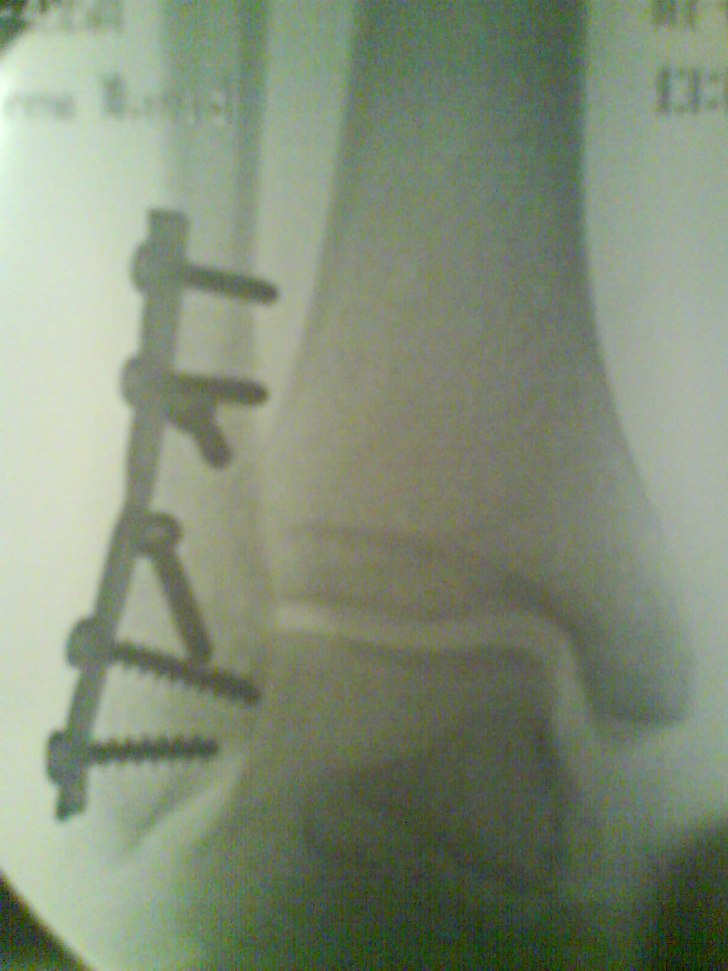

Efter ett misslyckat dropp

David Askengren

Östersunds Sjukhus (

Åre

Röntgenapparat